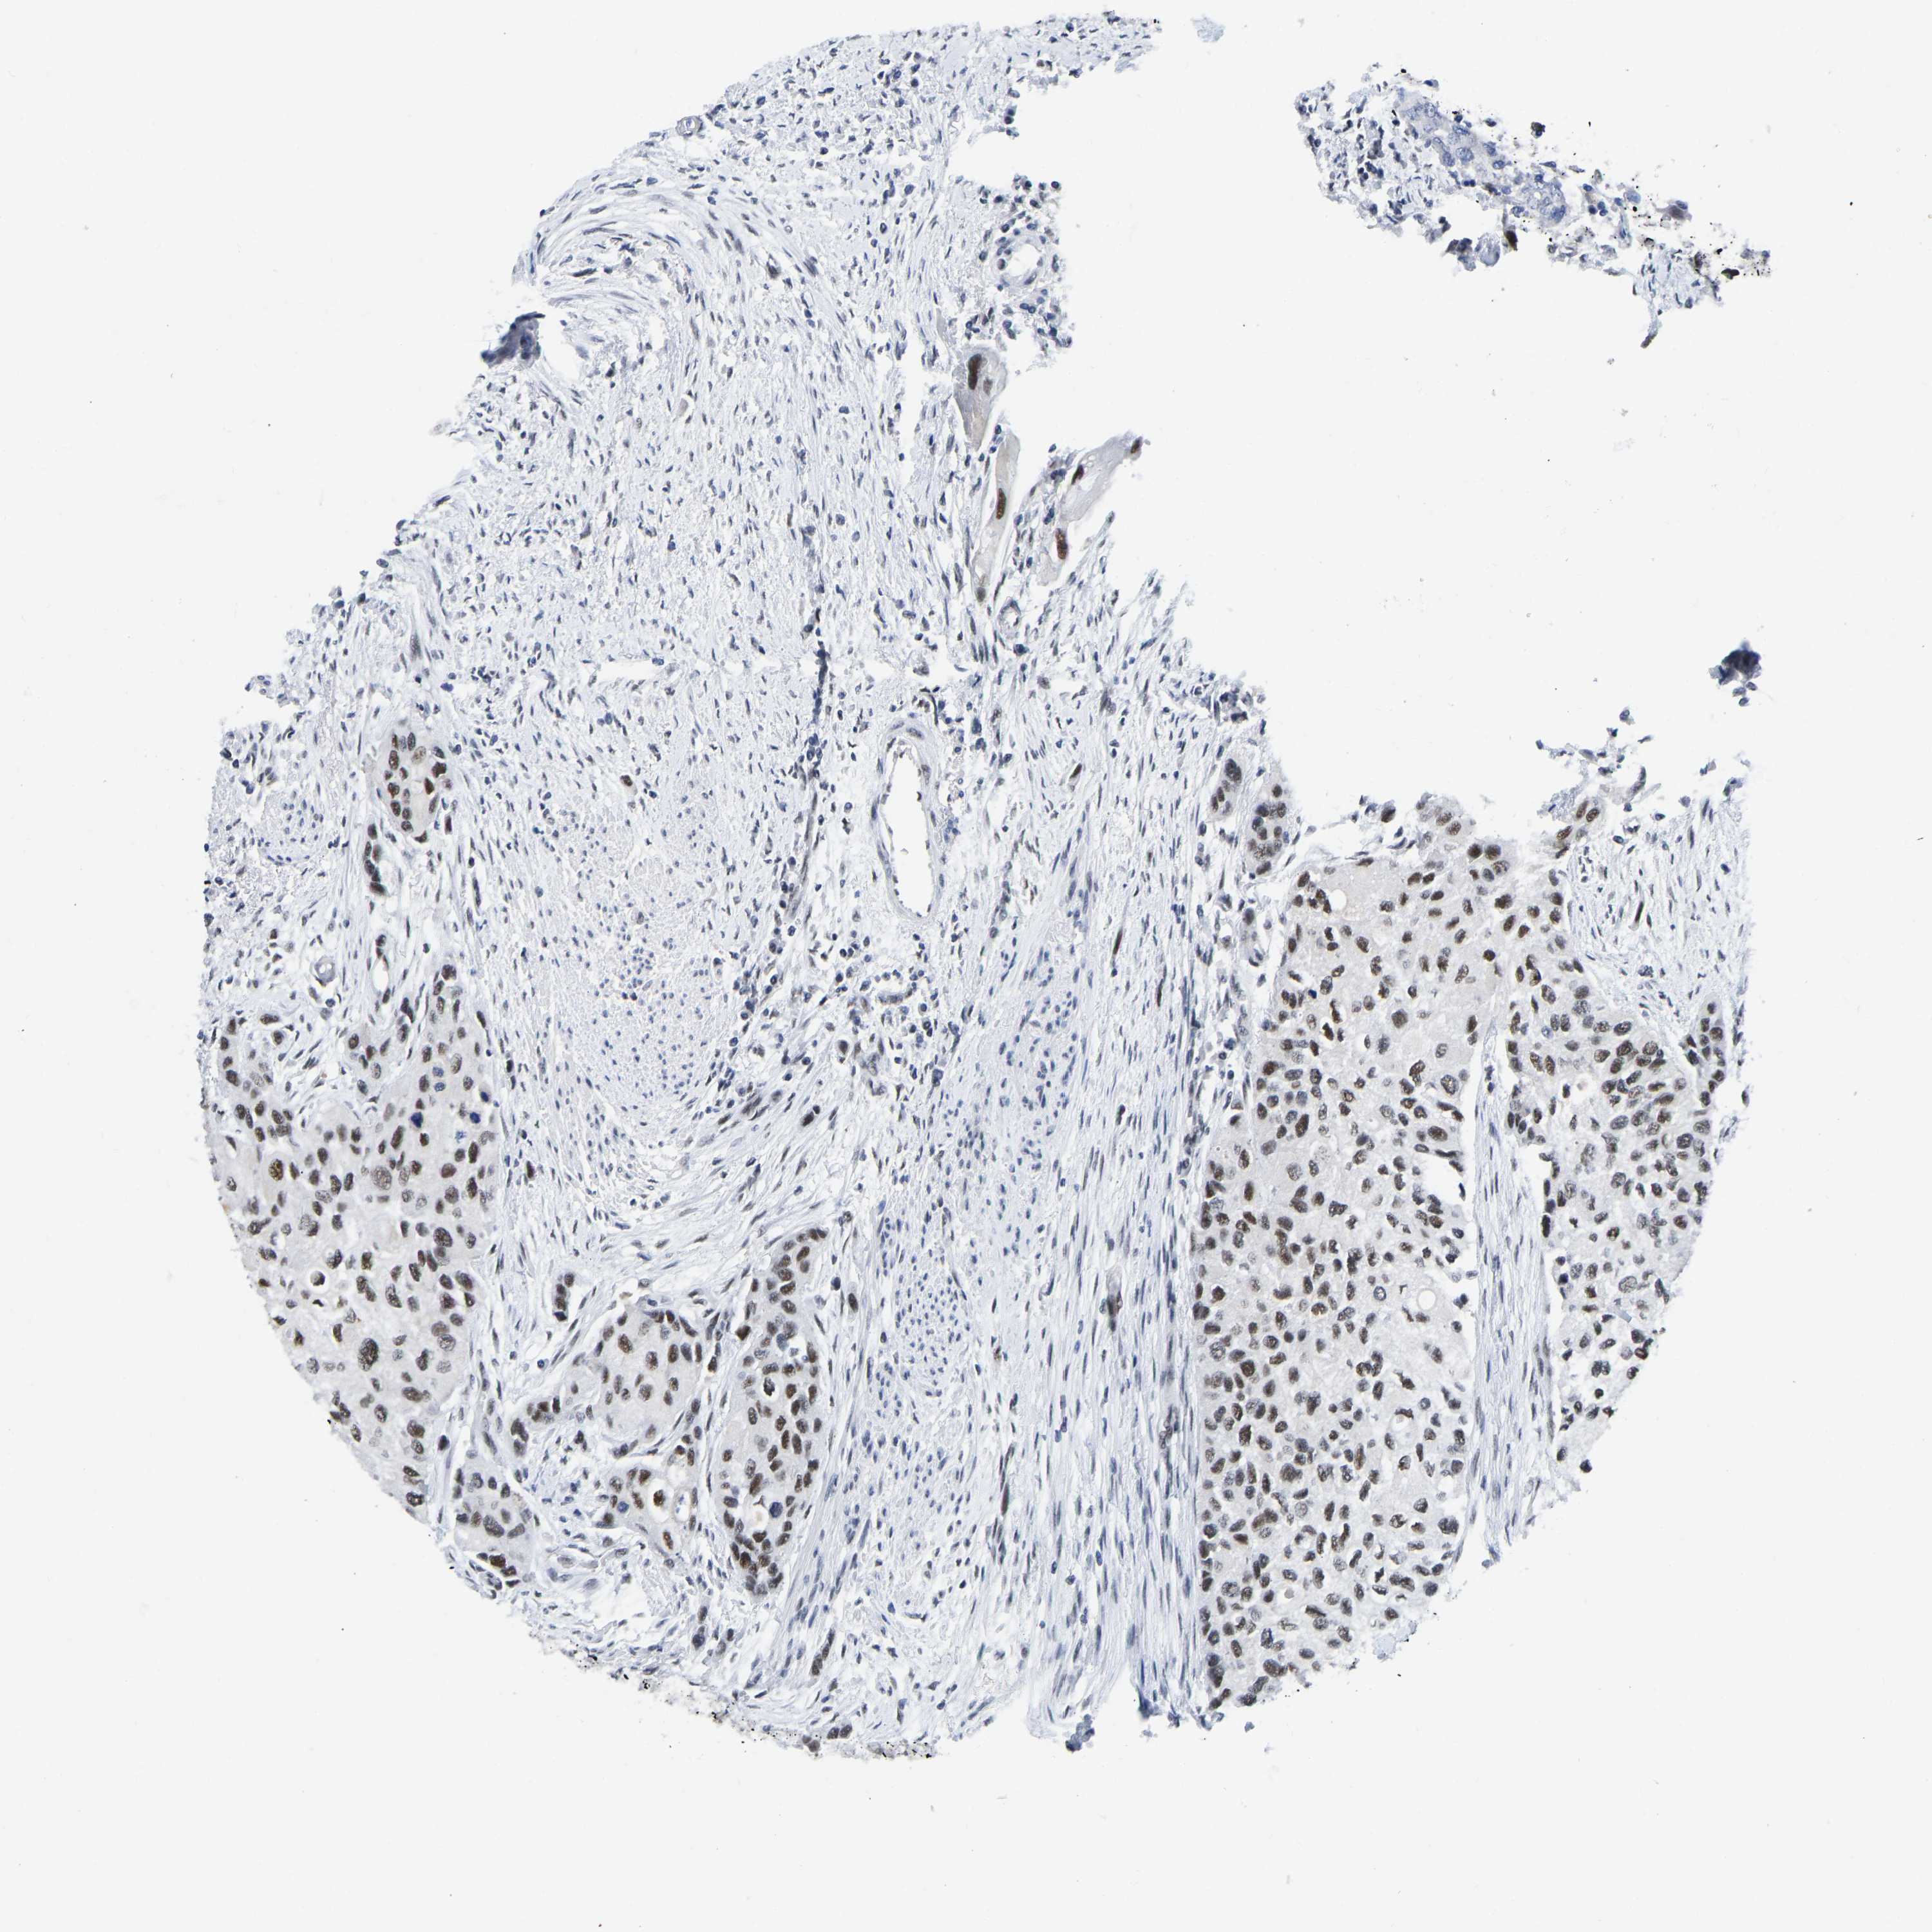

UROTHELIAL CANCER - Protein expressioni

A mouse-over function shows sample information and annotation data. Click on an image to view it in a full screen mode. Samples can be filtered based on level of antibody staining by selecting one or several of the following categories: high, medium, low and not detected. The assay and annotation is described here.

Note that samples used for immunohistochemistry by the Human Protein Atlas do not correspond to samples in the TCGA dataset.

Antibody stainingi

Antibody staining in the annotated cell types in the current human tissue is reported as not detected, low, medium, or high, based on conventional immunohistochemistry profiling in selected tissues. This score is based on the combination of the staining intensity and fraction of stained cells.

Each image is clickable and will lead to virtual microscopy that enables deeper exploration of all samples and also displays staining intensity scores, fraction scores and subcellular localization as well as patient and tissue information for each sample.

Antibody CAB019416

Staining

High

Medium

Low

Not detected

Intensity

Strong

Moderate

Weak

Negative

Quantity

>75%

75%-25%

<25%

None

Location

Urothelial carcinoma, Low grade

Urothelial carcinoma, High grade